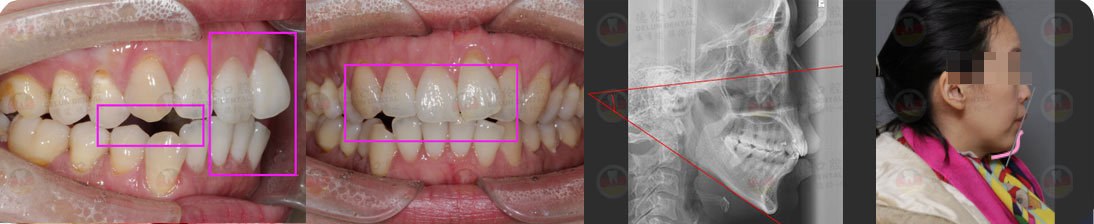

矯治采用兩種不同的厚度的膜片(牙套),發揮兩種不同膜片的各自優勢,在有效的作用時間內,矯治效率、矯治目標達成和舒適度方面較普通隱形矯正方式有明顯提升。

- 可預知

結合3D數字化口掃技術,可親自見證矯正后模擬效果圖

在保證矯正效果的情況下,大幅度縮短矯正時間

- 更準確

厚薄兩種矯治器,每周替換有利于牙齒位置的準確控制

- 更舒適 在不影響牙齒移動速度的前提下讓患者舒適度大大提高